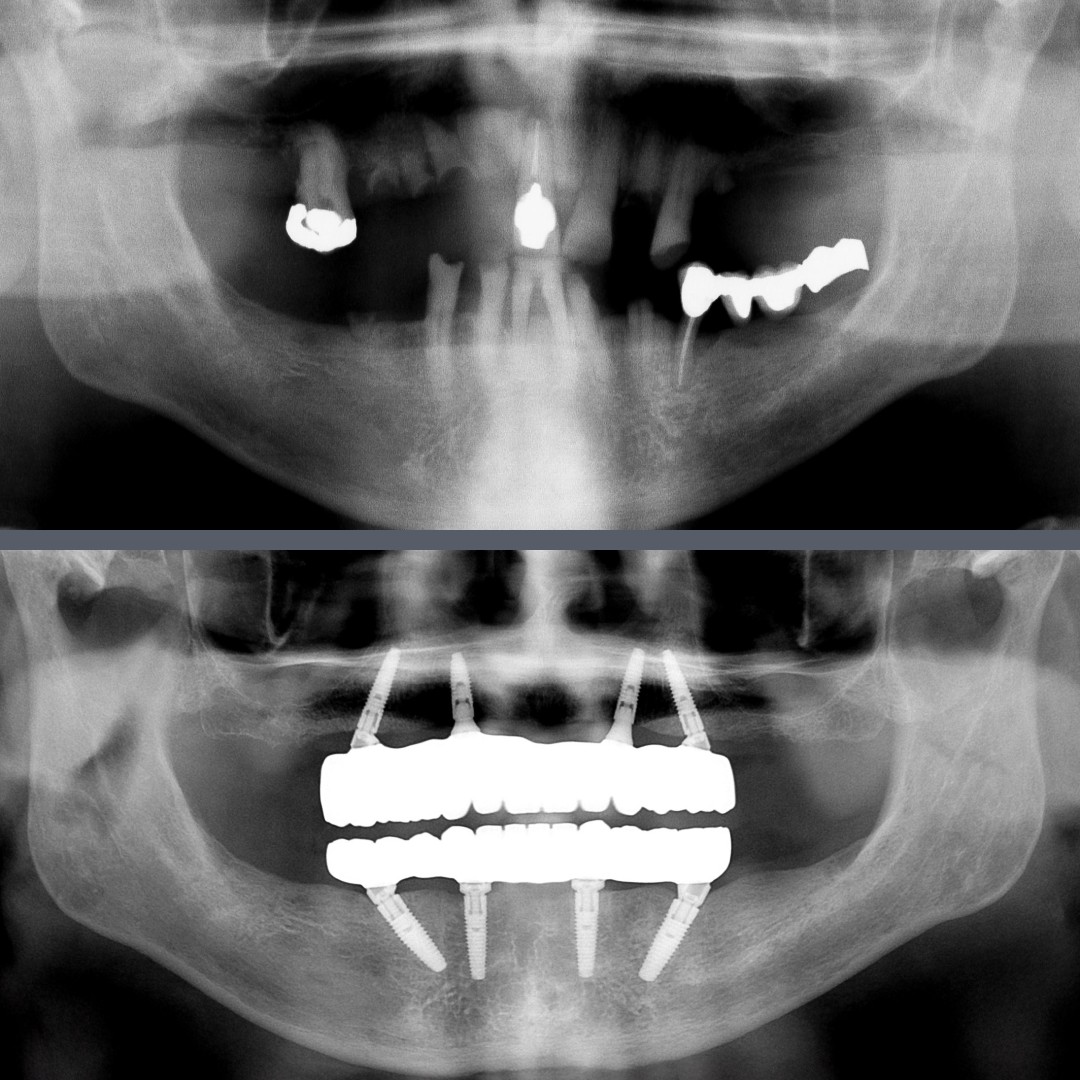

Severe Gum Disease and Tooth Loss – All-on-4®: Fixed Full-Arch Prosthesis in 48 Hours

The 74-year-old patient presented with advanced periodontitis and missing teeth. The remaining teeth were beyond saving, so full rehabilitation was necessary. Our goal was to provide a fixed solution that would quickly restore both chewing function and a natural smile, so we opted for the All-on-4® implantation method.

In the first session, we removed the unsalvageable teeth and placed four premium Nobel Biocare implants in both the upper and lower jaws. Within 48 hours of the surgery, the patient received fixed provisional All-on-4® bridges, offering immediate aesthetic and functional improvements.

The implants successfully integrated in less than six months, after which we could proceed with the final restorations. Using digital impressions, we created the permanent zirconia bridges that were carefully adjusted over multiple fittings. These final restorations provide a natural-looking, functional replacement.